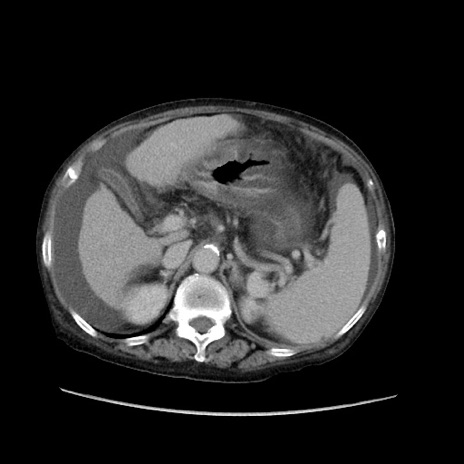

症例31(横断像)

【症例】80歳代 女性

【主訴】腹部膨満感

【現病歴】他院にて肝硬変にてフォロー中。1週間前から便秘、腹部膨満感、臍部腫瘤あり受診となる。

【既往歴】肝硬変

【身体所見】腹部膨隆あり、皮膚変化なし、疼痛なし。

【データ】WBC 4600、CRP 0.25